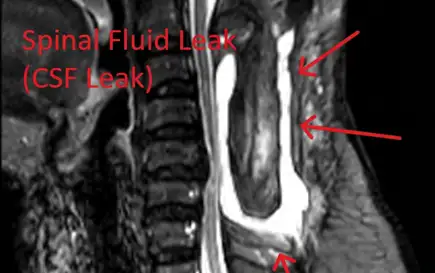

Spinal Fluid Leak

Dural tears leading to cerebrospinal fluid leaks, requiring additional repair surgery.